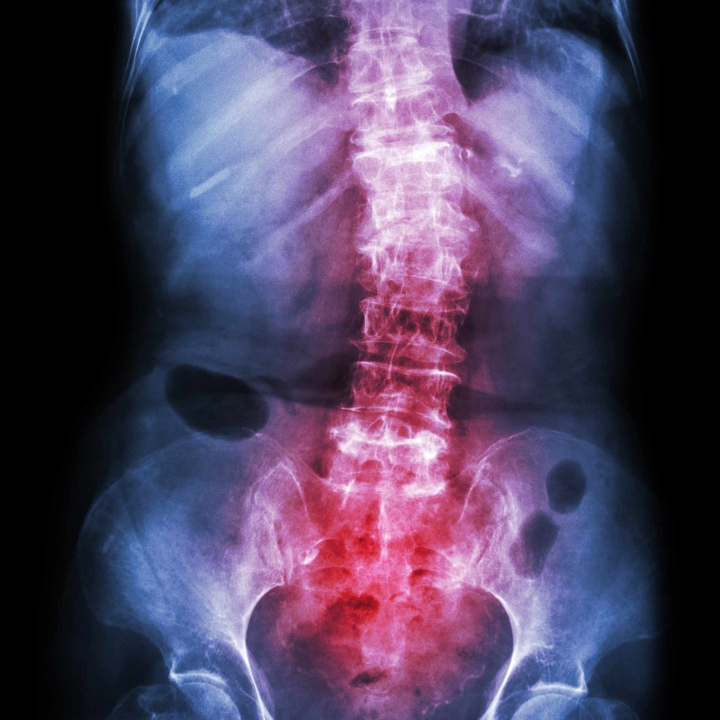

Болестта на Бехтерев анкилозиращи спондилит е вид артрит който засяга гръбначния стълб. Противно на общоприетото мнение това заболяване се диагностицира сравнително често. Симптомите включват болка и скованост от врата до долната част на гърба.

Болест на Бехтерев - причина за болка в гърба. Увеитът може да бъде първият симптом на болестта на Бехтерев понякога изпреварва появата на други признаци на заболяването в продължение на много години или да протича едновременно с участието на шията и гръбначния стълб. Симптомите при заболяването са причинени от възпаление в областта на гръбначния стълб ставите органите и последващите усложнения.

Заболяването протича с продължаващи месеци дори години болка и скованост в гръбначния стълб сакроилиачните и тазобедрените стави. Всеки ден едно и също. Болката в гърба е характерен симптом при болестта на Бехтерев и е на пристъпи.

Симптомите се изразяват в болка в очите фотофобия замъглено виждане белодробна фиброза сърдечна недостатъчност и др. Дорзолумбалгия засягане на гръбначния стълб или който причинява възпалителни болки в гръбнака. Симптомите на анкилозиращ спондилит включват болка и скованост от шията до долната част на гърба.